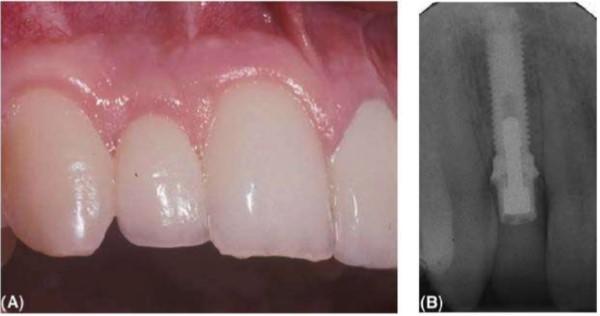

(A) Răng cửa bên hàm trên được thay thế bởi một implant cho thấy hình dạng mô mềm tốt và thẩm mỹ. (B) Hình ảnh X quang của implant, trường hợp này đường kính nhỏ khoảng 3.3 mm Nobel Biocare. Implant đường kính nhỏ thích hợp cho vị trí chịu lực ít.